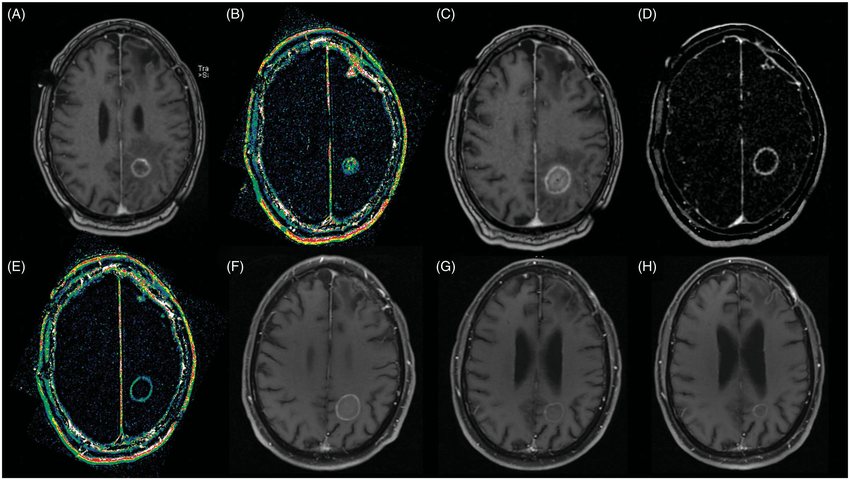

临床经验分析表明,脑肿瘤手术切除的程度与预后密切相关,目前手术原则仍是在顺利的前提下较大范围地切除肿瘤。经研究总结,很多长期生存的患者经过了规范化的手术,实现较大范围的肿瘤顺利切除,复发后手术仍是优选的治疗策略。

INC国际神经外科医生集团专注于中外神经外科技术的交流、合作、促进和提高,同时针对高要求人群及特别疑难手术病例提供咨询服务。INC温馨提示,脑瘤复发是个国际难题,我们尚未攻破,但也并非束手无策。比如对于复发性胶质瘤的治疗,目前仍以手术为主,辅助放、化疗等综合治疗。手术的适应症与原则的把握、手术方式、技巧和手术辅助技术的应用,都直接影响着肿瘤的切除和并发症的发生。

另外,4级胶质瘤如果复发在功能区,便不建议再次手术;病变与大脑非功能区可考虑手术治疗;肿瘤分级2-3级,表浅复发建议再次手术。而根据患者情况,如果年龄较高,身体一般情况较差的,也不建议再次做手术。